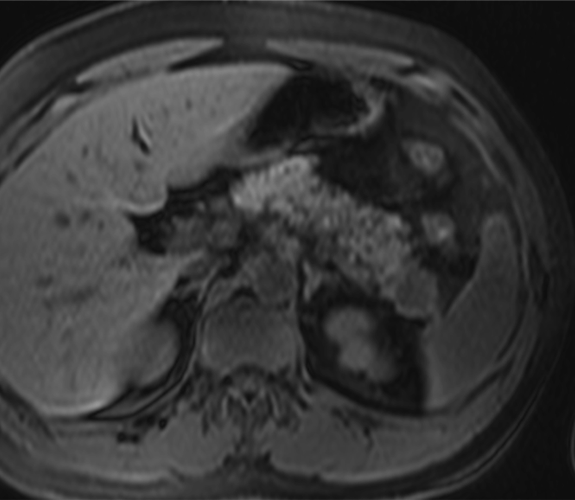

Hombre de 39 años con antecedente de fibrosis retroperitoneal.

Se solicita TC porque en RM externa realizada para control de la fibrosis retroperitoneal se informa de sospecha de neoplasia de cola de páncreas.

3. ¿Cuál es tu diagnóstico?

- A. Tumor pseudopapilar sólido pancreático con metástasis renales izquierdas.

- B. Linfoma pancreático -forma localizada- y lesiones atróficas renales izquierdas secundarias a fibrosis retroperitoneal.

- C. Lesión metastásica en páncreas de tumor primario renal.

- D. Pancreatitis autoinmune en contexto de enfermedad relacionada con la IgG4.

- E. Sarcoidosis con afectación pancreática y renal.